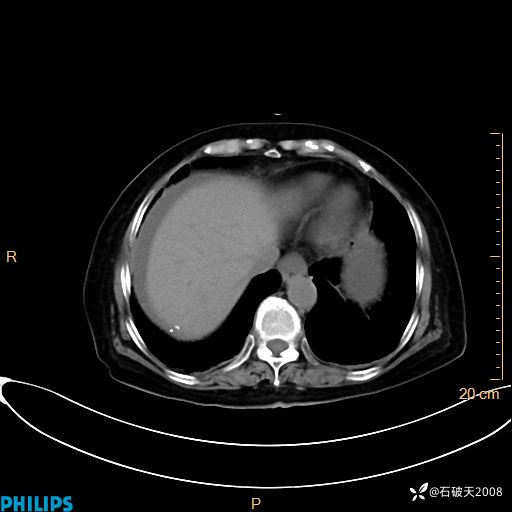

MIP